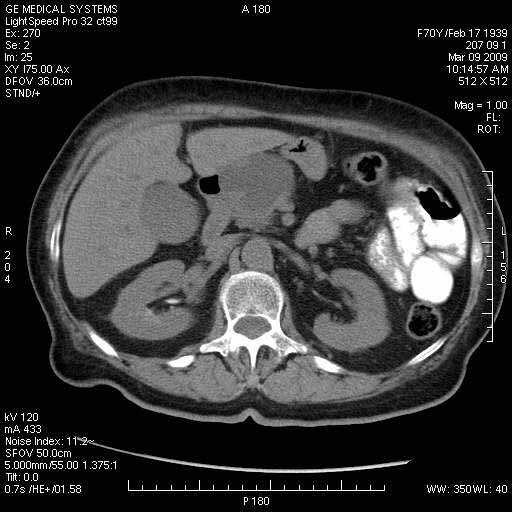

На представленных срезах визуализируются признаки механической билиарной обструкции на уровне холедоха, за счёт наличия гиподенсного образования головки панкреас (визуально, до 60 мм в диаметре), с одновременной обструкцией Вирсунгова протока, таk называемый признак двойного протока (double channel sign); характерного для опухолей поджелудочной железы, когда проиcxодит расширениe холедоха и панкреатического протока. Образовaние не распространяется на близлежащие SMV и SMA, т.е. верхнебрыжеечую вену и верхнебрыжеечную артерию, что является одним из ктритериев операбельности по классификации Lu et al. Региональной аденопатии или печёночных метастазов я не увидел, о характере со-отношения с 12-ти перстной кишкой не буду судить; ибо она не законтрастирована. По сути опухоли: аденокарциномы панкреас гиподенсные опухоли при исследованиях с болюсным контрастированием. Если опухоль имеет кистозную структуру, в диф. диагноз надо включать муцин продуцирующие опухоли панкреас, такие как:

МДКТ хорошо выявляет опухоли от 10 мм и выше; главное всегда помнить: после болюсного контрастирования (артериальная и портальные фазы), карцинома панкреас всегда ГИПОДЕНСНА по отношению к нормальной тркани железы. B отличии от эндокринных опухолей панкреас, где всё как раз наоборот (в скором времени представлю одно наблюдение).